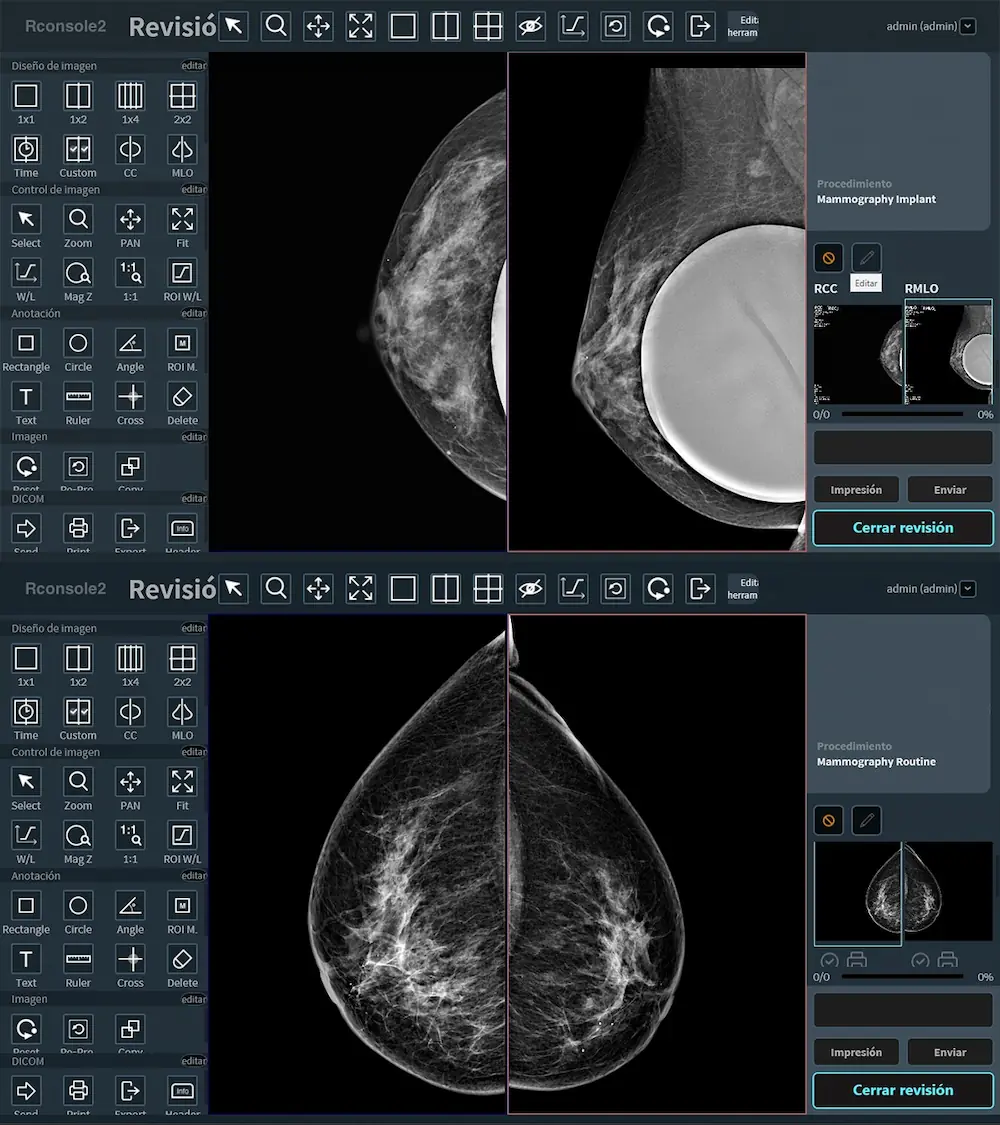

¿Qué tan importante es captar hasta el más mínimo detalle en una mamografía? ¿Puede una imagen de baja resolución comprometer la detección de lesiones en etapas tempranas? En el diagnóstico por imagen, especialmente en el estudio de las mamas, cada milímetro cuenta. La resolución espacial, es decir, la capacidad de un sistema para distinguir estructuras muy pequeñas y cercanas entre sí, se ha convertido en un factor determinante para detectar microcalcificaciones, nódulos sutiles o distorsiones arquitectónicas que podrían pasar desapercibidas con tecnologías convencionales.

Hoy, gracias a los avances en mamografía digital, la mejora continua en detectores, algoritmos de reconstrucción y técnicas de reducción de ruido permite obtener imágenes con una definición excepcional. Esta evolución no solo impacta en la precisión diagnóstica, sino también en la confianza del especialista y la seguridad de la paciente.

La resolución espacial es uno de los factores determinantes para detectar lesiones en etapas tempranas, cuando aún no son palpables ni visibles clínicamente. Esta capacidad para diferenciar estructuras muy pequeñas dentro del tejido mamario influye directamente en la sensibilidad del estudio y en la posibilidad de actuar de forma oportuna ante signos incipientes de cáncer.

- Visualización clara en tejidos densos: en mujeres con mamas densas, la resolución espacial es crítica. Permite diferenciar estructuras superpuestas y evitar que una lesión quede oculta entre tejidos fibroglandulares.

- Mejora en la calidad de reconstrucción tridimensional: en mamografía digital 3D o tomosíntesis, una mayor resolución espacial contribuye a generar cortes más definidos, facilitando la revisión capa por capa de la mama.

- Mejor visualización en mamas densas: las pacientes con tejido mamario denso tienen mayor riesgo de desarrollar cáncer y son más difíciles de evaluar. La mejora en la resolución y la reducción de ruido aumentan las posibilidades de detectar lesiones ocultas entre el tejido fibroglandular.